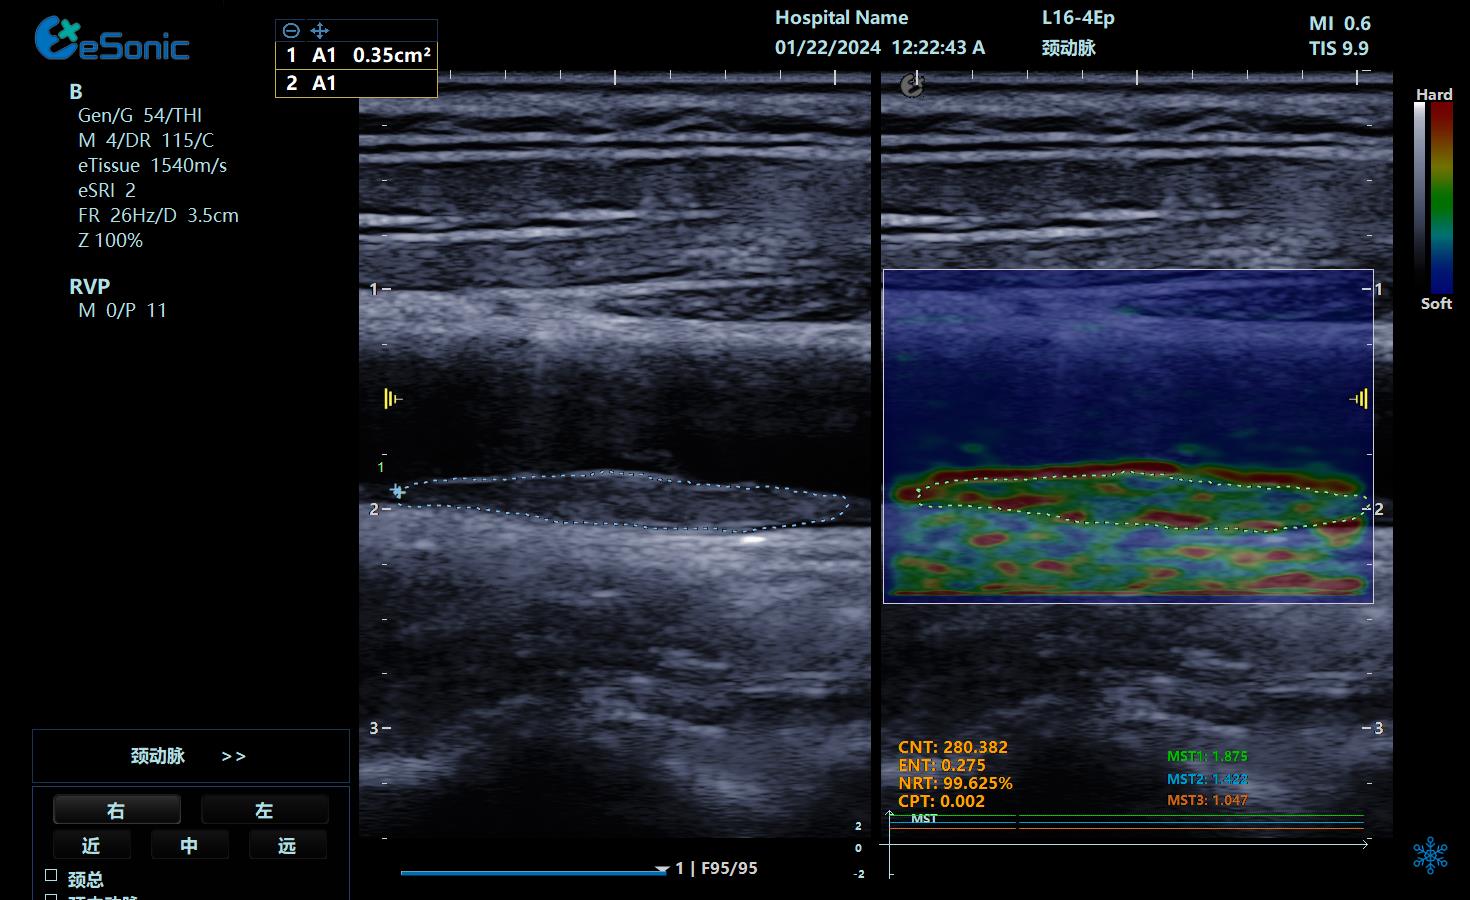

业内首创RVP原始数据斑块定量评估技术,量化评估颈动脉斑块风险程度。

RVP原始数据斑块定量评估技术